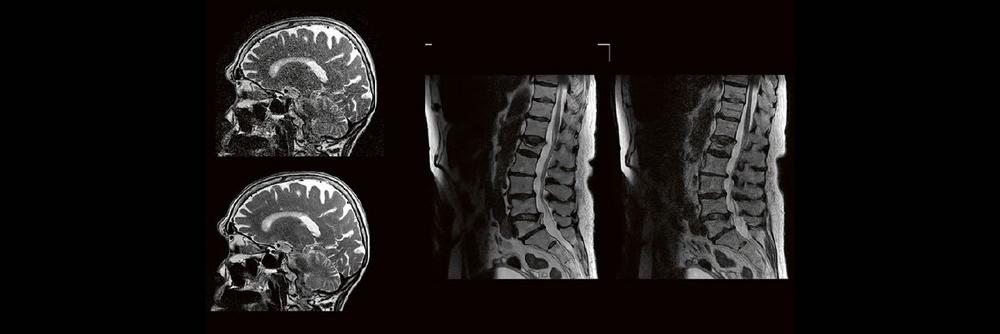

Outside the box-Vortrag: die Neuroradiologie der Moral (Webinar | Online)

Professor Dr. med. Michael Knauth Das Treffen moralischer Entscheidungen erfordert – wie jede andere Hirnleistung auch – das Zusammenwirken verschiedener Hirnareale. Der Vortrag nimmt auf eine interaktive Reise durch die Mehrzügeligkeit moralischer Entscheidungen (emotional vs. utilitaristisch) und gängiger moralischer Dilemmata (Trolley-Problem) und führt schließlich zu den mit dem Treffen dieser Entscheidungen befassten Hirnregionen und zu […]

MR-Spektroskopie: Hintergründe und Anwendung im klinischen Alltag – Teil 2 (Webinar | Online)

Dr. med. Urspeter Knecht Die MR-Spektroskopie – eine oft unterschätze Untersuchungsmethode – kann im Rahmen eines molekularen Fingerprints ein Game Changer sein in der neuroradiologischen Bildgebung. Eine Zusammenstellung von Hintergründen, Pitfalls, Aha-Erlebnissen, Nutzen und Risiken – Teil 2 Eventdatum: Mittwoch, 22. November 2023 17:00 – 18:00 Eventort: Online Firmenkontakt und Herausgeber der Eventbeschreibung: Canon Medical […]